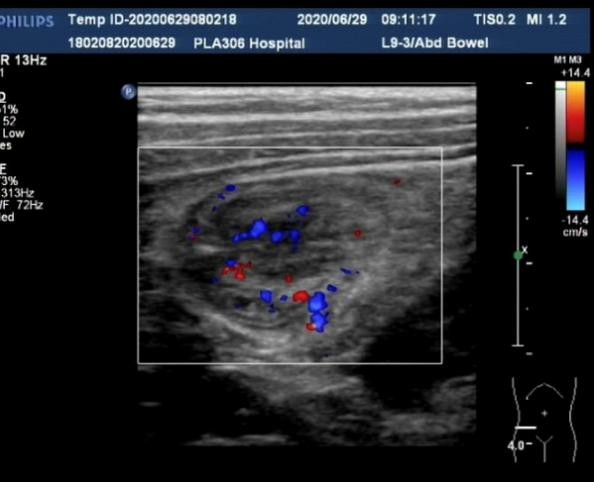

超声表现:腹部可探及包块,横断面呈多层"同心圆"征(图3),纵断面呈多层肠管平行排列的"套筒"征(图4),超声多普勒检查提示包块内血流信号呈点状散在分布(图5);或观察到动静脉频谱,提示肠管受压的症状轻,循环良好,包块内未显示血流信号或血流信号稀少,提示肠管可能存在缺血坏死的症状。部分患儿包块及周围肠系膜内可探及增大的淋巴结(图6)。

图5. 肠套叠横切彩色血流超声图像